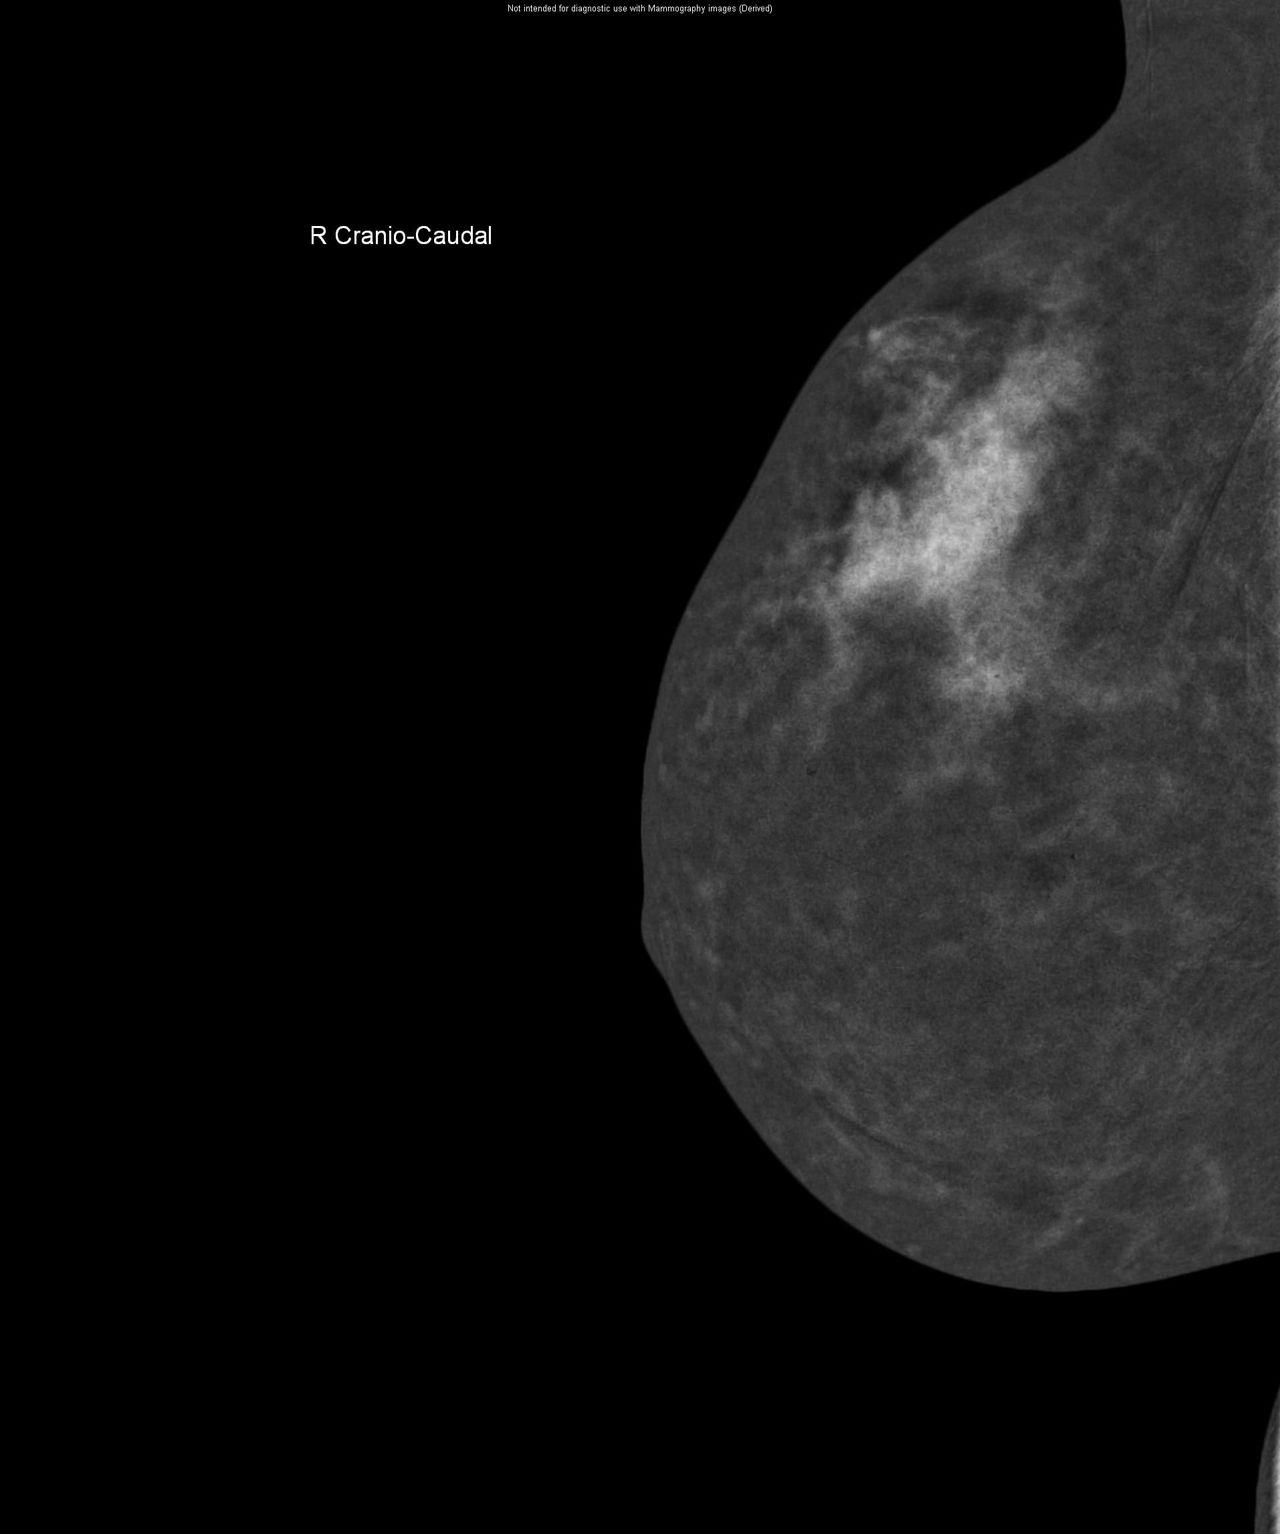

CESM is an advanced form of mammography that uses a safe dye injected into the bloodstream. This dye highlights areas of concern within the breast, giving clinicians a much clearer and more detailed image than a traditional mammogram.

“Sometimes it can be difficult to interpret a mammogram, especially in patients with dense breast tissue”, Nicole explains. “It’s a bit like looking for a cloud in a sky full of clouds. The contrast helps remove that ‘noise’ and shows us exactly what’s going on inside the breast.”

“A patient came to us with a lump in one breast. When we used CESM, we also spotted abnormality in the other breast. This enabled both breasts to be dealt with at the same time which would not have been possible otherwise.”